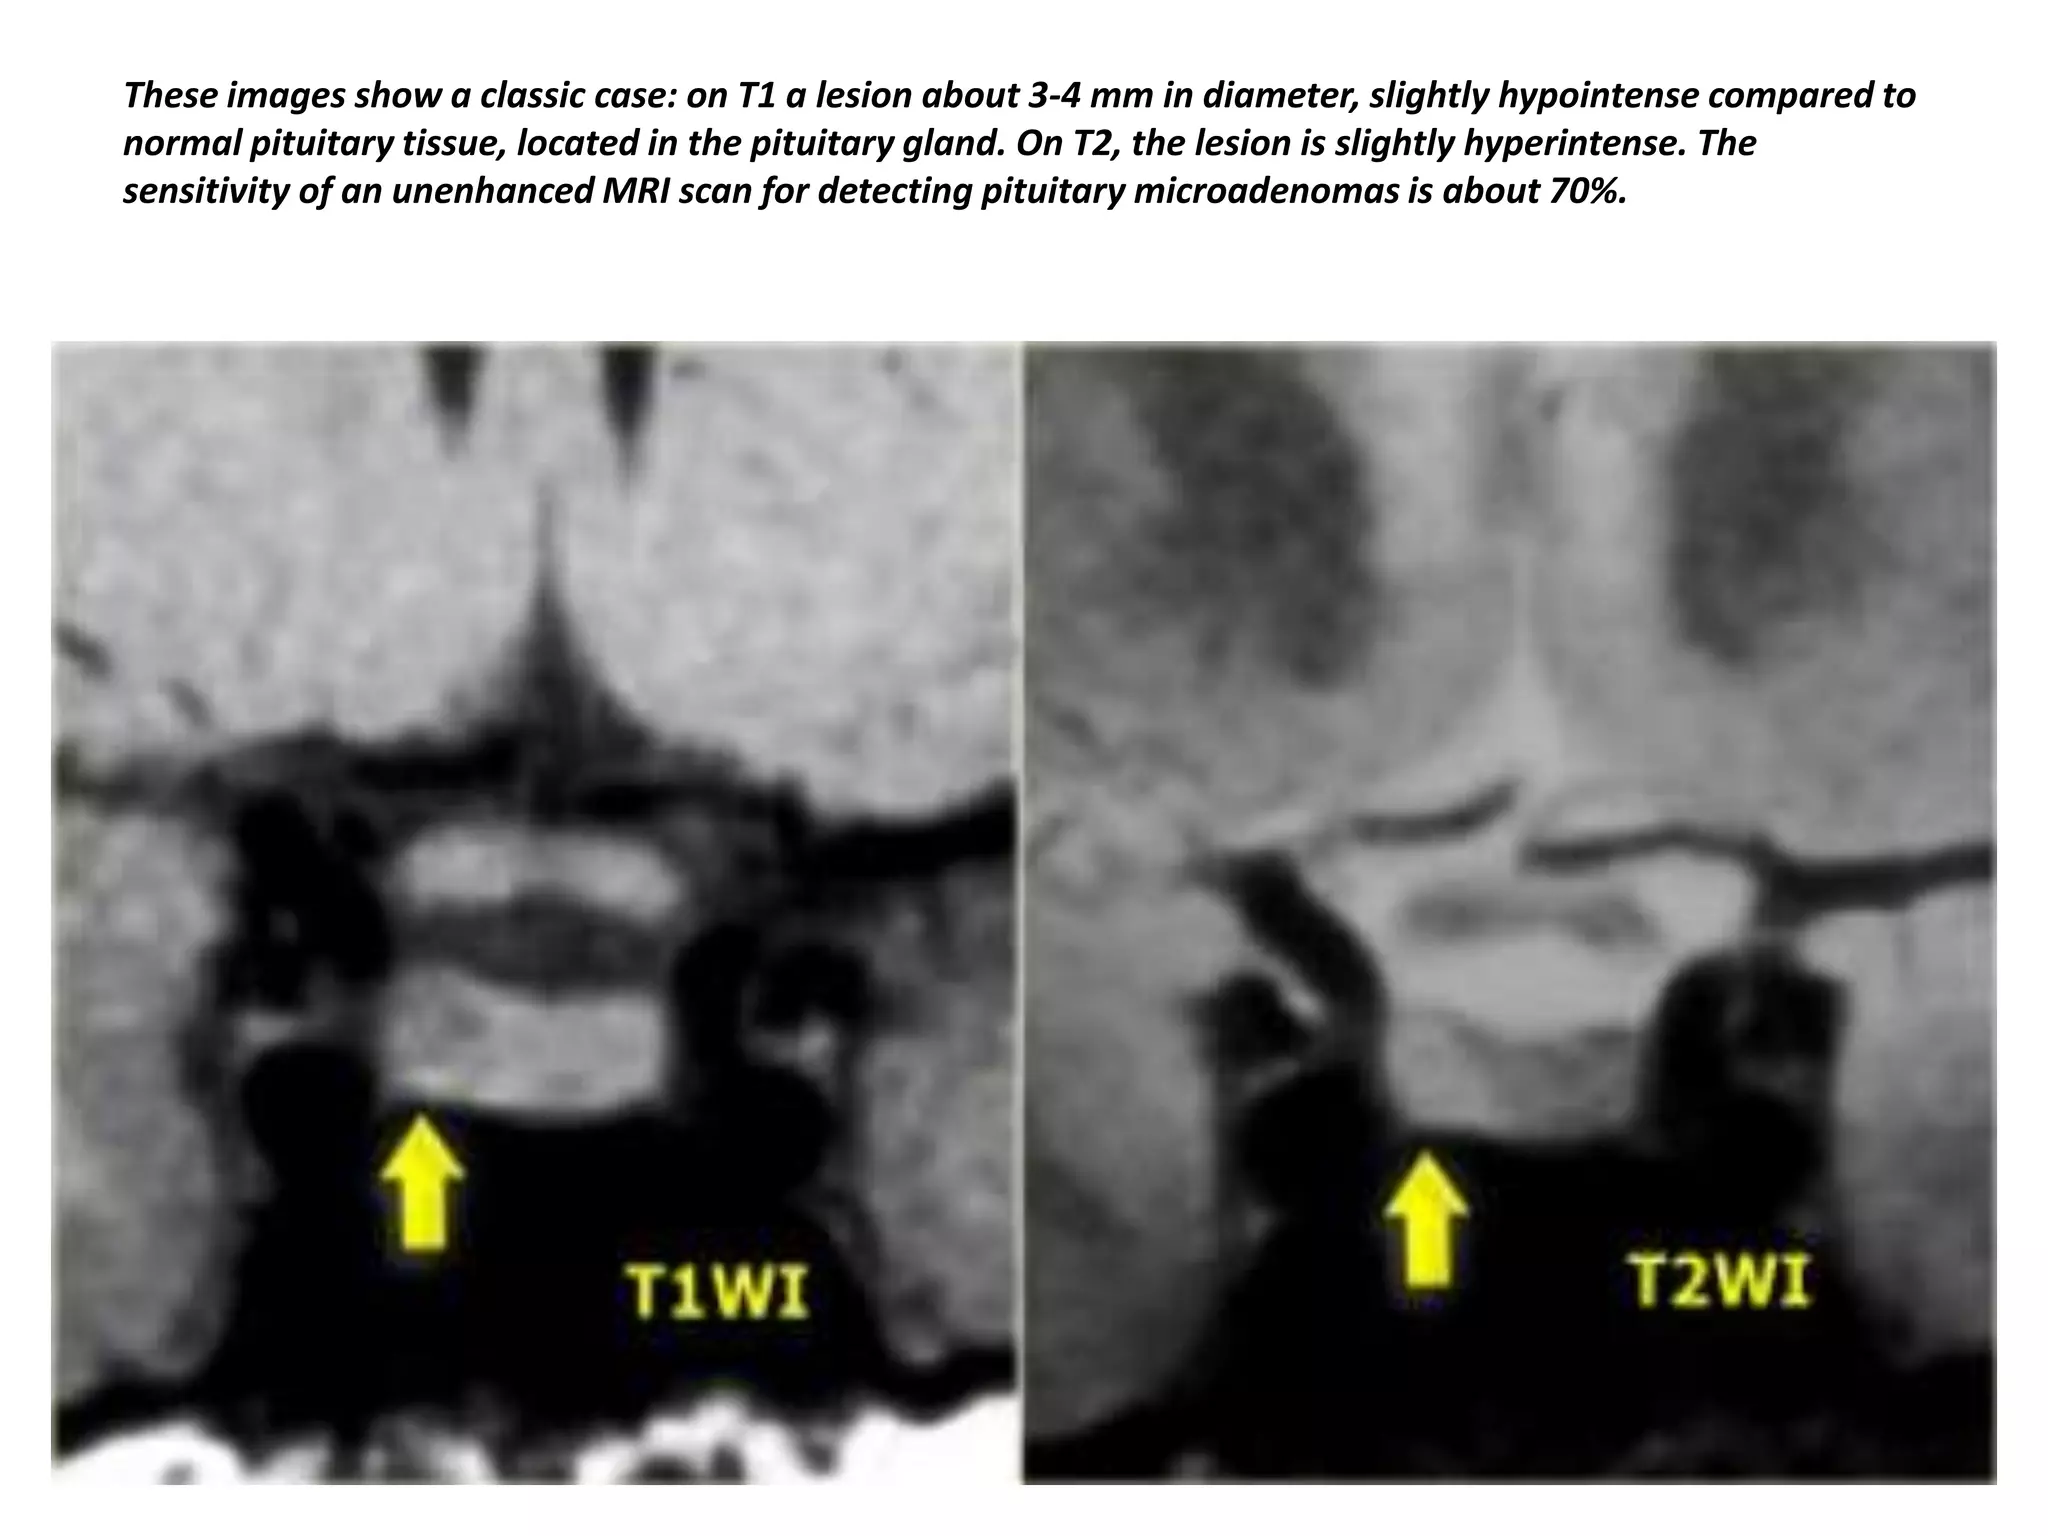

These images show a classic case: on T1 a lesion about 3-4 mm in diameter, slightly hypointense compared to

normal pituitary tissue, located in the pituitary gland. On T2, the lesion is slightly hyperintense. The

sensitivity of an unenhanced MRI scan for detecting pituitary microadenomas is about 70%.